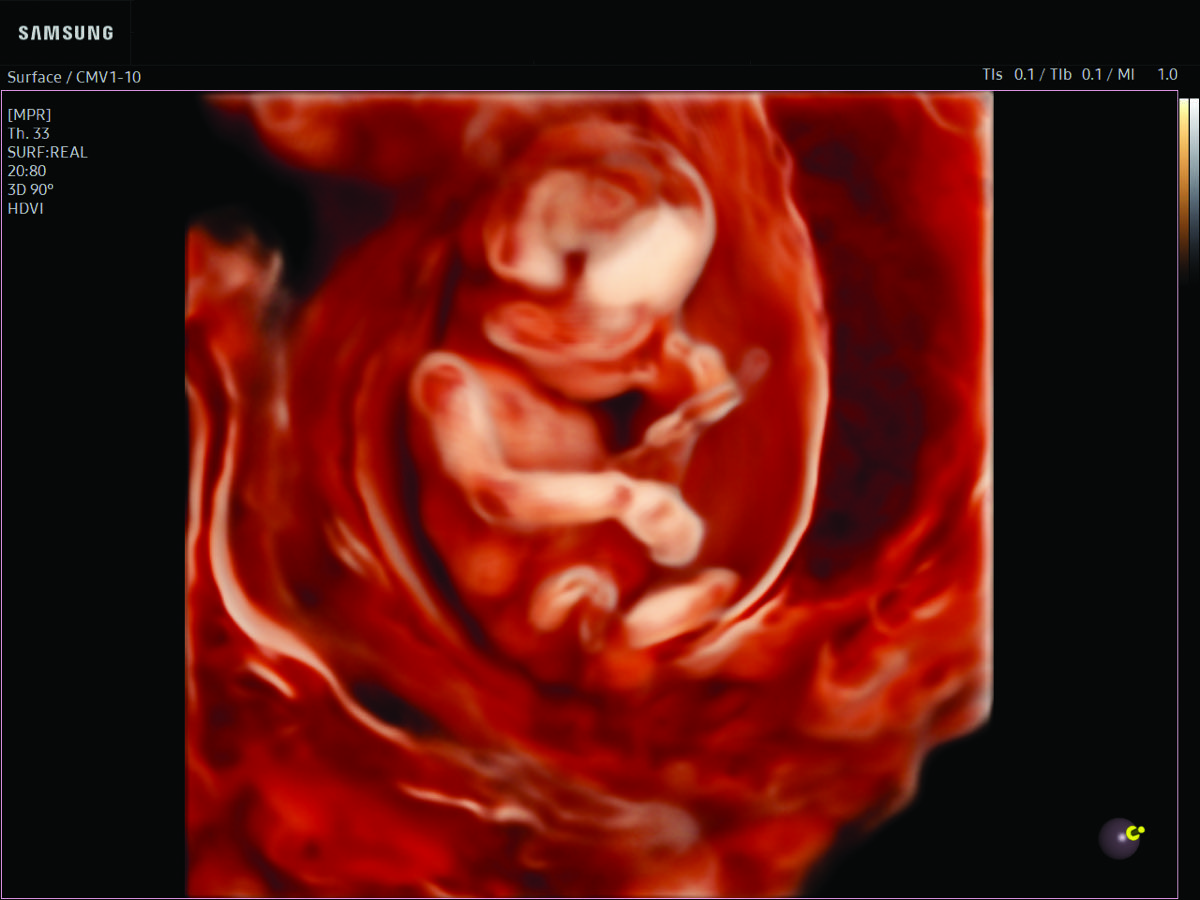

Comprehensive, advanced and expert MFM care for high-risk pregnancies

- Fetal anomalies